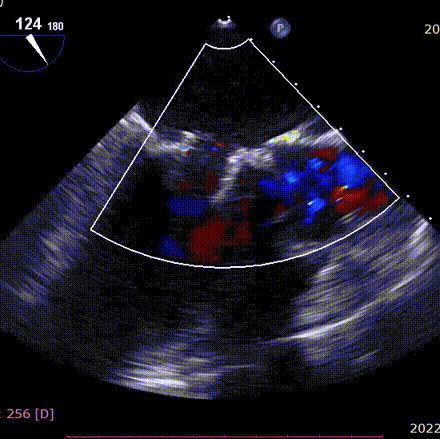

术前TEE显示大量反流

术后TEE显示反流情况明显改善